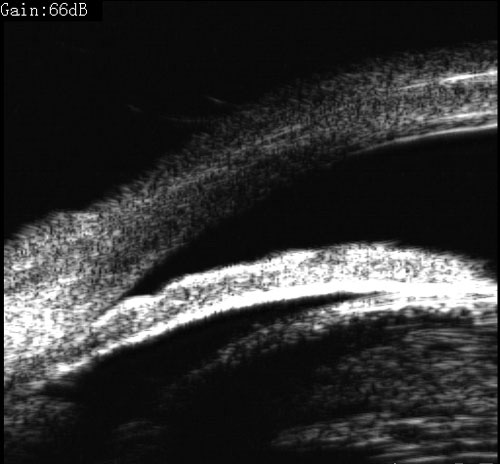

青光眼合并白内障